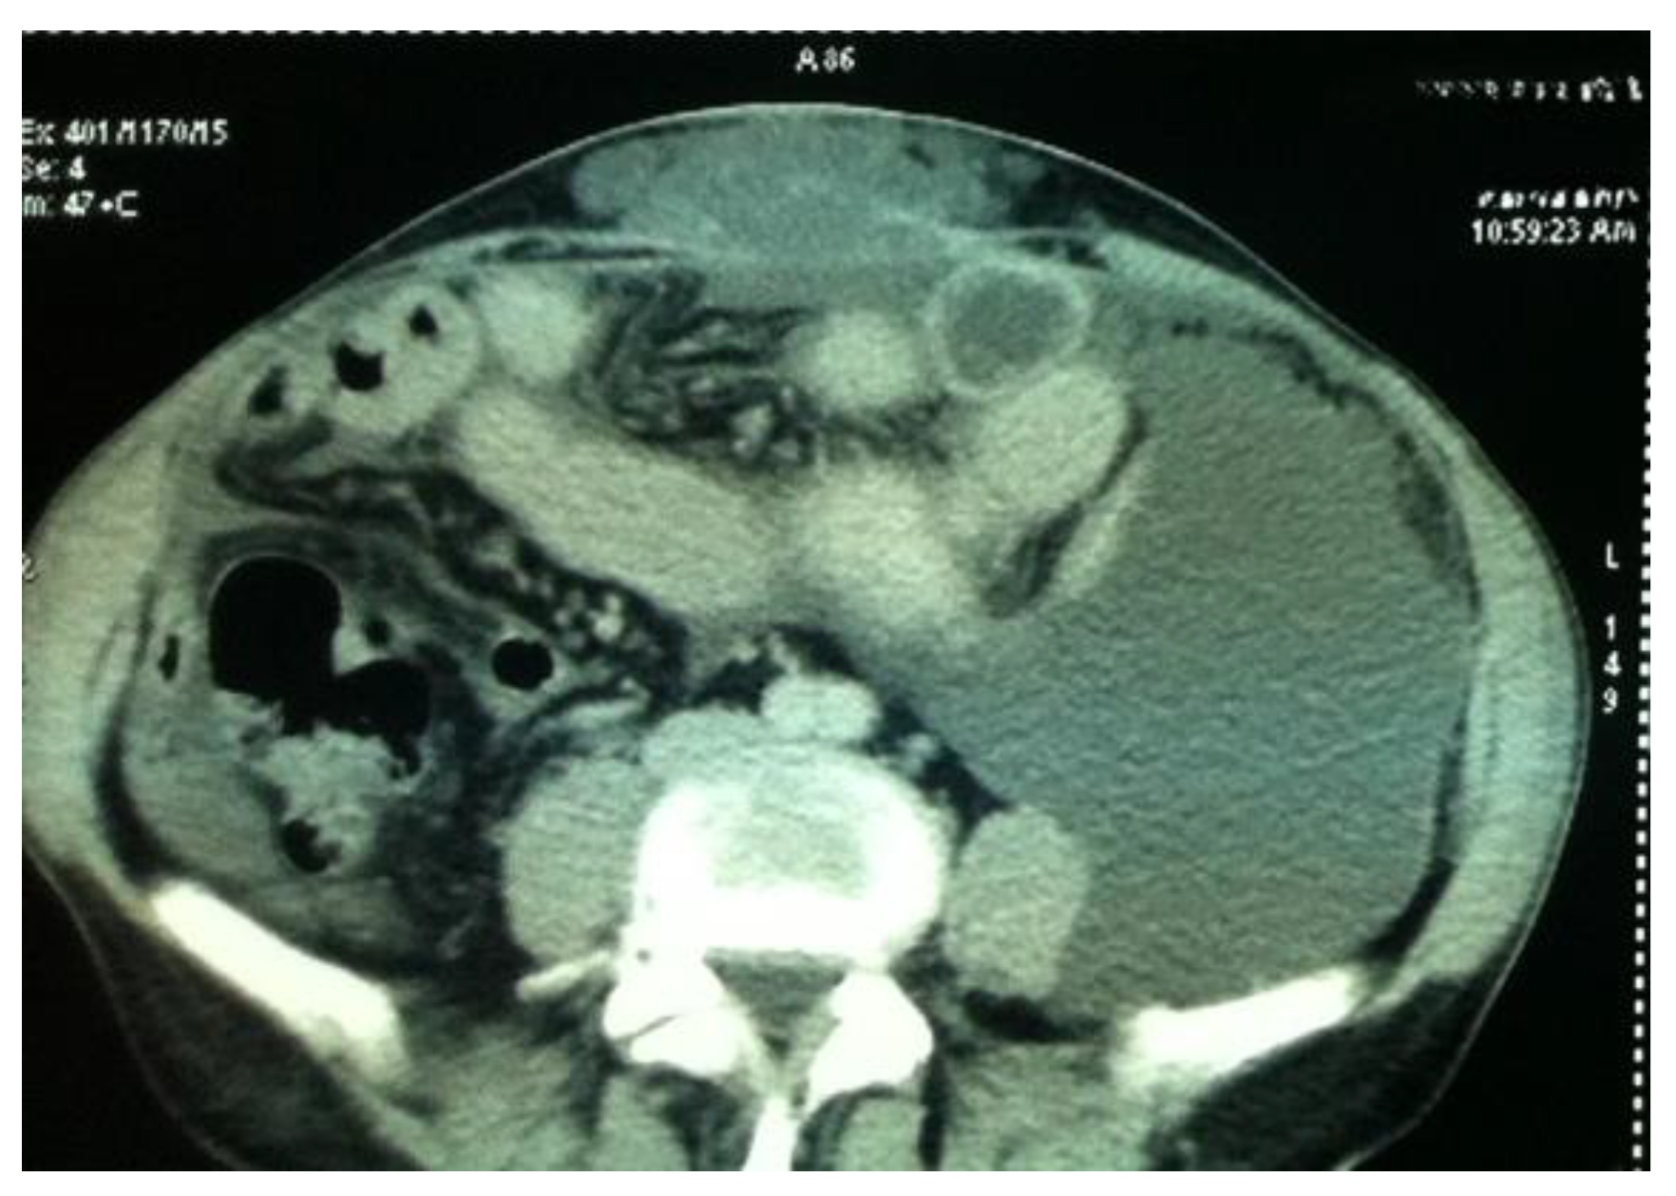

Imaging is essential in differential diagnosis and the diagnosis of the primary tumor, as well as in the assessment of the index of peritoneal carcinomatosis and tumor recurrence (Figure 1).

Currently, contrast-enhanced abdominopelvic computer tomography (CT) is the imaging modality of choice for diagnosing pseudomyxoma peritonei [9,10,11,12]. The typical CT appearance of the liver and spleen surfaces is scalloped, caused by loculated mucin accumulations, which helps distinguish mucin from fluid ascites [10,11].

However, CT has a limited performance in the detection of metastatic adenopathy, with a sensitivity of 41% and a specificity of 89%, a fact that influences the decision regarding infrarenal lymphadenectomy [13]. In addition to underestimating metastatic adenopathy, CT also underestimates the presence of peritoneal metastases, especially in the presence of ascites or mucin accumulations specific to pseudomyxoma (Figure 2).

Therefore, the peritoneal carcinomatosis index PCI) is underestimated in CT evaluations. This influences the decision regarding the therapeutic attitude and the selection of patients for cytoreduction or neoadjuvant chemotherapy (Table 1).

Figure 2. CT aspect of PP; evaluation of secondary peritoneal and intestinal metastases is affected by the presence of mucin in the left flank.